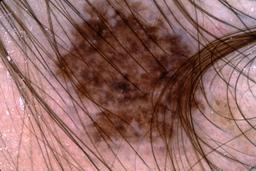

{

"age_approx": 65,

"anatom_site_general": "head/neck",

"concomitant_biopsy": true,

"dermoscopic_type": "contact non-polarized",

"diagnosis_1": "Malignant",

"diagnosis_2": "Malignant melanocytic proliferations (Melanoma)",

"diagnosis_3": "Melanoma, NOS",

"diagnosis_confirm_type": "histopathology",

"image_type": "dermoscopic",

"lesion_id": "IL_2174824",

"melanocytic": true,

"patient_id": "IP_8355925",

"sex": "male"

}